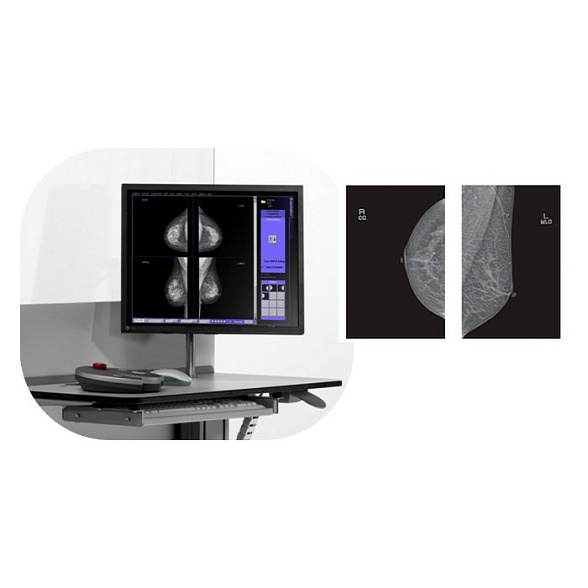

- Рентгенология